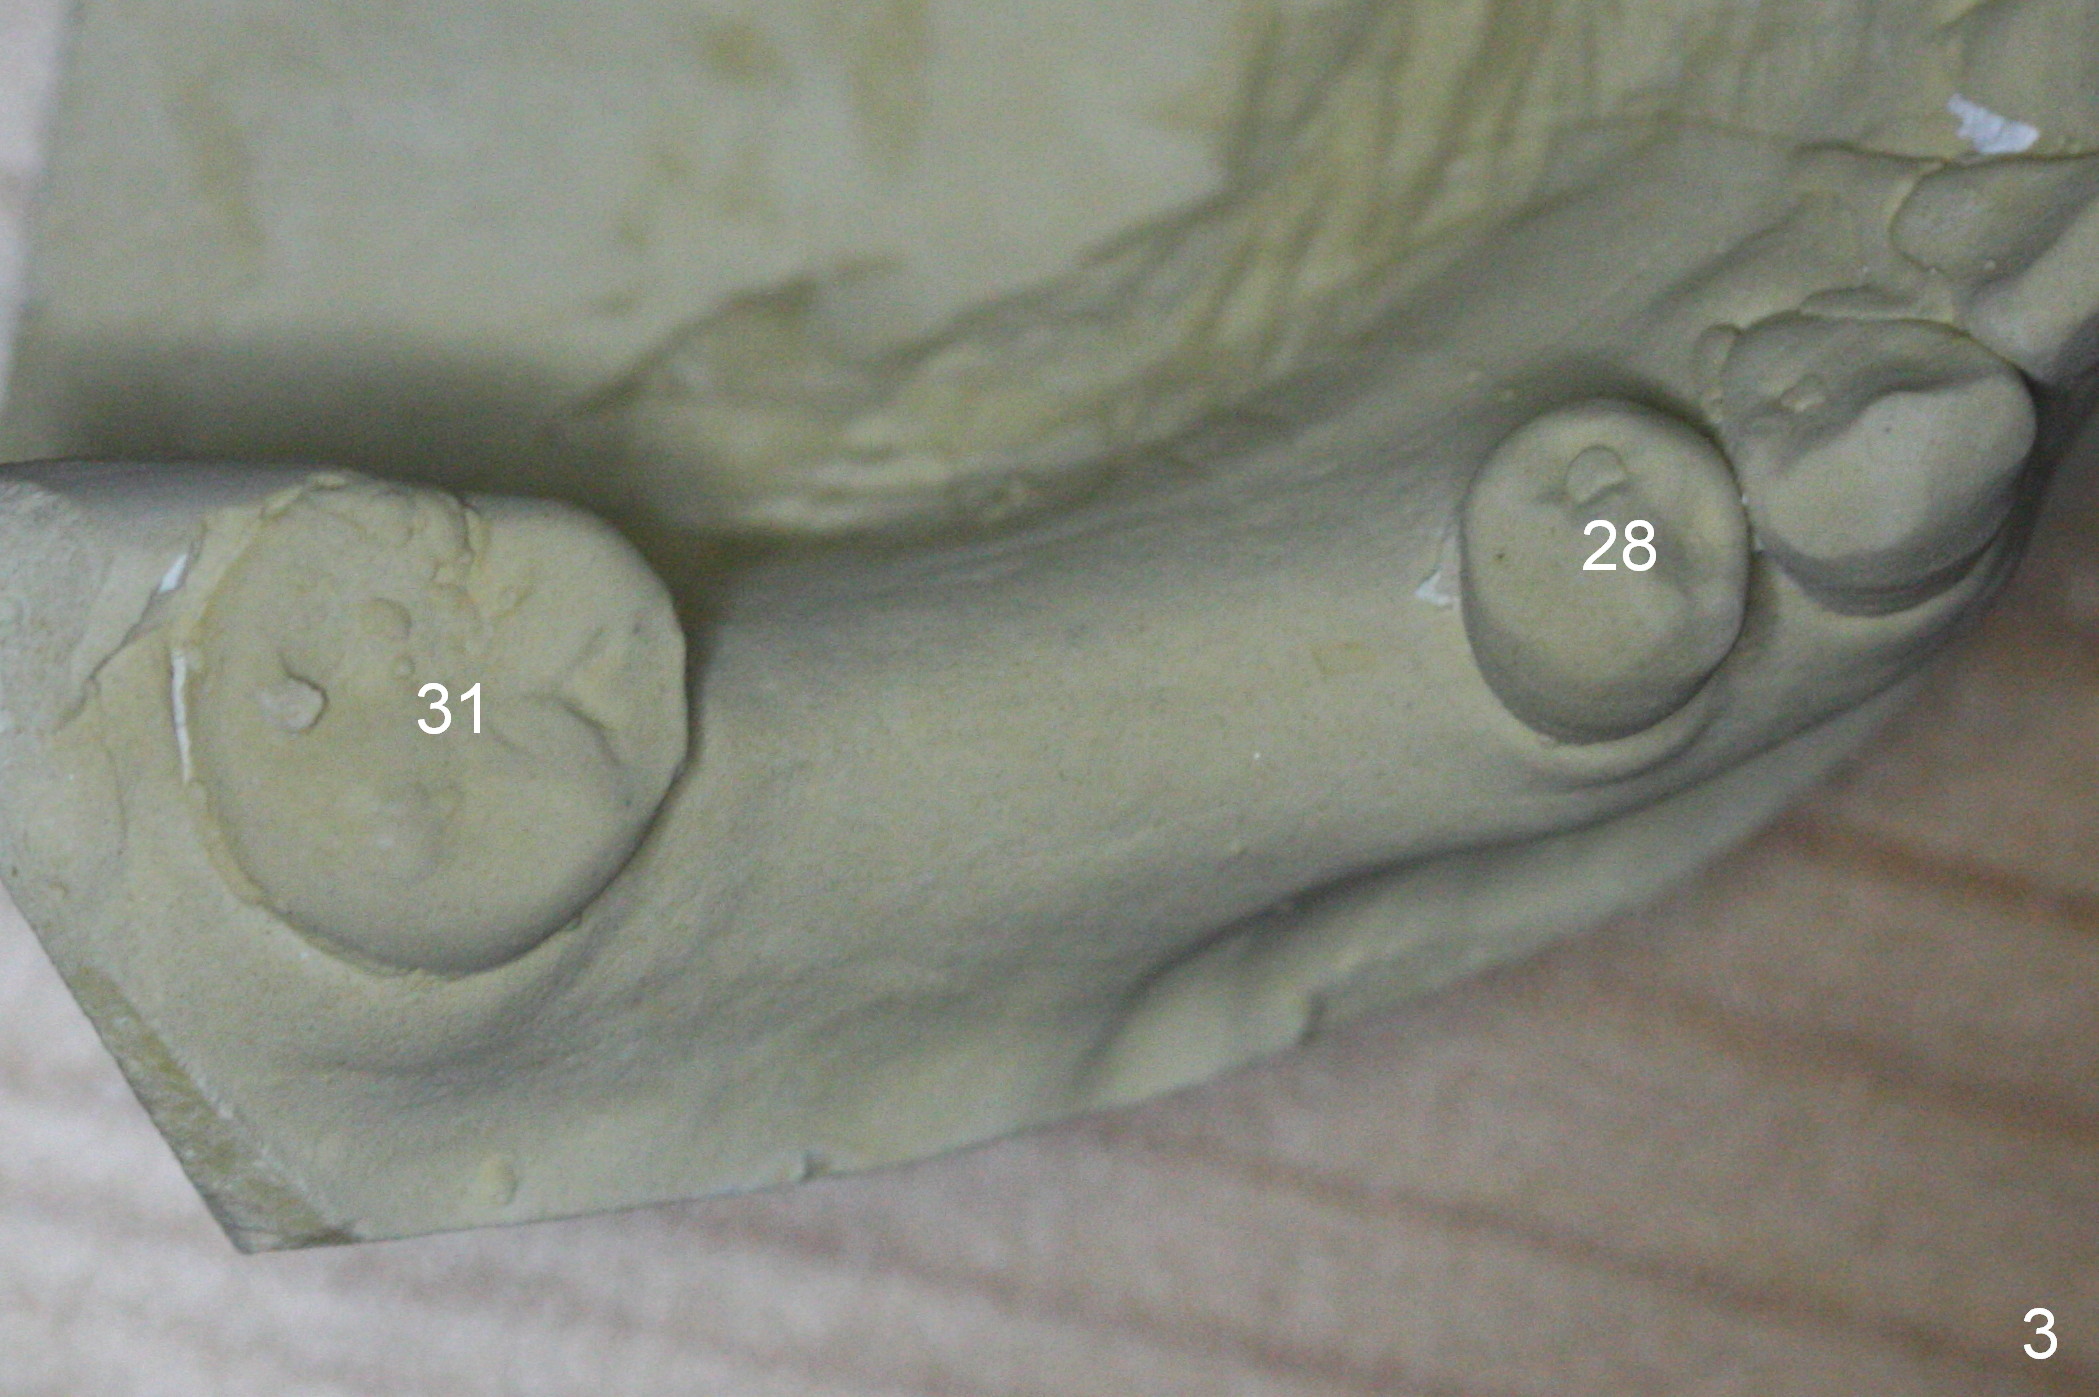

The ridge appears to be not so narrow (Fig.3). The opposing teeth (#3-5) are slightly supraerupted (Fig.4).